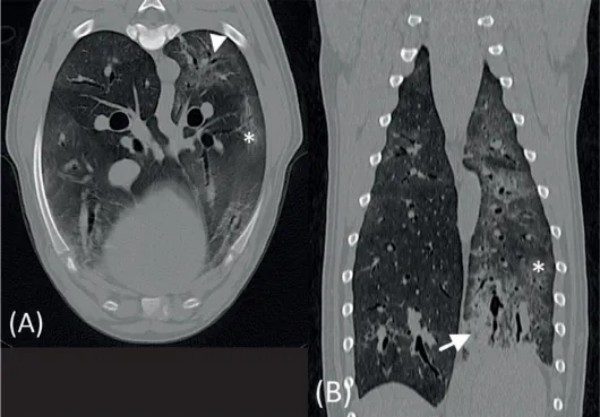

影像学、诊断与结果 在全身麻醉下使用1.5特斯拉磁共振成像系统对脑部和颈椎进行了MRI检查。获得的序列和成像平面包括:T2加权横断面图像、T2加权矢状面图像、T2加权液体衰减反转恢复背面图像、磁敏感加权成像横断面图像、扩散加权成像和表观扩散系数横断面图像、平扫及增强后T1加权横断面图像、T1加权背面图像。图像由一位委员会认证的兽医放射科医生和一位正在培训的兽医放射科医生使用软件以数字格式进行评估。 MRI显示右侧顶叶区域有一个边界清晰、卵圆形的轴内肿块,测量大小为(图1)。该病变对大脑镰产生显著的占位效应,导致中度向左的中线移位和双侧侧脑室的中度局部受压。该肿块在T2加权图像中与灰质呈等信号,依赖侧可见高信号的液-液平面,在T1加权序列和DWI序列中呈低信号,在ADC图中呈等信号。在T2加权以及SWI序列中,可见一薄而清晰的边缘低信号环勾勒出病灶轮廓。静脉注射钆对比剂后,肿块显示出微弱的边缘强化。周围白质在T2加权和FLAIR序列中显示出明显的、边界不清的高信号,在T1加权增强扫描中无强化。MRI结果与右侧顶叶急性轴内出血伴病灶周围实质水肿一致。T1加权低信号和T2加权等信号的表现以及病灶周围水肿支持急性病变。未发现其他脑部病变。 图1初次就诊时不同序列的脑部MRI图像:A, T2加权横断面和 B, 矢状面,C, 磁敏感加权序列和 D, 对比注射后T1加权序列(图片左侧为患者右侧)。在右侧顶叶,可见一个边界清晰、轴内、圆形至卵圆形、T2加权等信号和T1加权低信号的病变(星号),伴有薄层周边对比增强(白色箭头)。注意磁敏感加权序列中的低回声边缘,T2加权序列中围绕病变的黑边(黑色箭头),以及T2加权高信号的液-液线。病变周围白质存在边界不清的T2加权高信号,符合病灶周围水肿(箭头)。病变对大脑镰和侧脑室显示出中度的占位效应。T2 W, T2加权; T1 W, T1加权。 为了进一步调查凝血障碍的根本原因并评估合并症,使用CT扫描仪对胸部和腹部进行了CT检查。使用OsiriX MD进行了肺窗重建。 所有肺叶均显示明显的、中度的非结构性间质至肺泡肺模式,并伴有周边加重(图2)。观察到广泛的轻度支气管壁增厚,伴有多灶性支气管周围袖套征。总之,混合性肺模式及其周边加重最符合血管圆线虫感染引起的寄生虫性肺炎。可能性较小的鉴别诊断包括肺微出血、其他物种(例如狐环体线虫)引起的寄生虫性肺炎、细菌性或慢性支气管炎以及间质性肺炎。 基于这些发现,进行了贝尔曼-韦策尔幼虫迁移试验,发现了少量血管圆线虫幼虫。随后,开始了治疗方案,包括两次滴剂应用吡虫啉 400 mg/莫西克丁 100 mg,间隔2周。值得注意的是,在第一次滴剂治疗后仅3天,神经系统症状就有显著改善。这些症状逐渐改善,并在初次就诊后6周完全消失。 图2初次就诊时使用肺窗的肺部计算机断层扫描图像,A, 横断面视图,和 B, 背 面视图(图片左侧为患者右侧)。注意所有肺叶中周边加重的间质(星号)和肺泡(白色箭头)浸润。可以观察到广泛的支气管增厚伴支气管周围袖套征(箭头)。 尽管临床症状完全消失,6周后在同一机构使用相同的采集参数进行了脑部MRI检查,以持续监测右侧颞叶病变。获得的序列和成像平面包括:T2加权横断面图像、T2加权矢状面图像、T2加权 FLAIR 背 面图像、T1加权横断面图像、平扫及增强后T1加权 背 面图像、DWI和ADC横断面图像、SWI横断面图像。图像由与6周前相同的专家使用相同的程序进行评估。与之前的MRI扫描一致,在右侧顶叶检测到一个边界不清、形状不规则的T2加权低信号病变,中心呈T2加权高信号(图3)。该病变在T1加权上呈低信号,SWI呈均匀的信号缺失。在DWI和ADC序列中呈低信号,测量大小为 1.1 cm × 0.6 cm × 0.6 cm。静脉注射钆对比剂后未观察到对比增强。邻近的脑实质未见异常。 图3初次就诊后6周不同序列的脑部MRI图像:A, T2加权横断面和 B, 矢状面,C, 磁敏感加权图像和 D, 对比注射后T1加权图像(图片左侧为患者右侧)。与初次就诊相比(见图1),右侧顶叶实质内病变尺寸显著减小。它显示出边界不清的T2加权低信号轮廓,中心为高信号(星号)。T1加权序列显示低信号病变,无对比增强(白色箭头)。在SWI序列中观察到明显的信号缺失(黑色箭头)。未再注意到病灶周围T2加权高信号。T2 W, T2加权; T1 W, T1加权; SWI, 磁敏感加权成像。 总之,该病变符合缓解期的慢性轴内出血,缺乏病灶周围水肿。随后的血液检查显示VWF无进一步异常,颊粘膜出血时间在正常参考范围内。截至稿件准备之时,该犬临床表现正常。 讨论